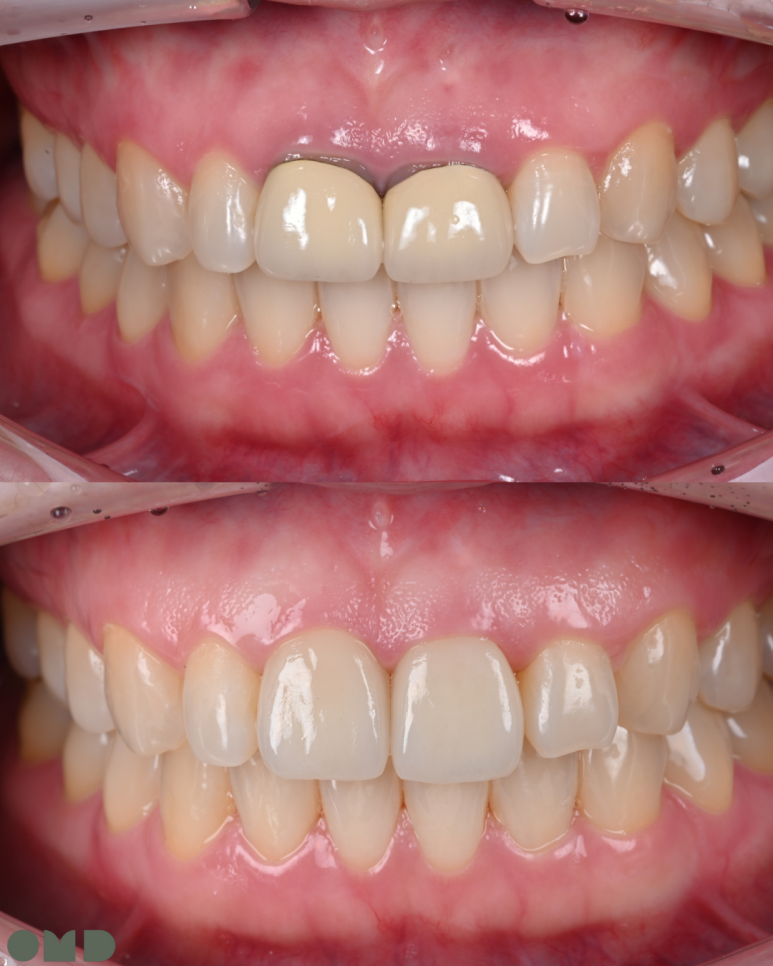

약 3주의 기간 동안 크라운 주변 잇몸이 잘 적응한 것을 확인 할 수 있었습니다.

25.08.11 임시치아 장착

25.09.04 임시치아 장착 약 3주 후

25.09.11 치료 후

앞니 크라운은 심미적으로 가장 눈에 띄는 부위라

작은 차이에도 만족도가 크게 달라집니다.